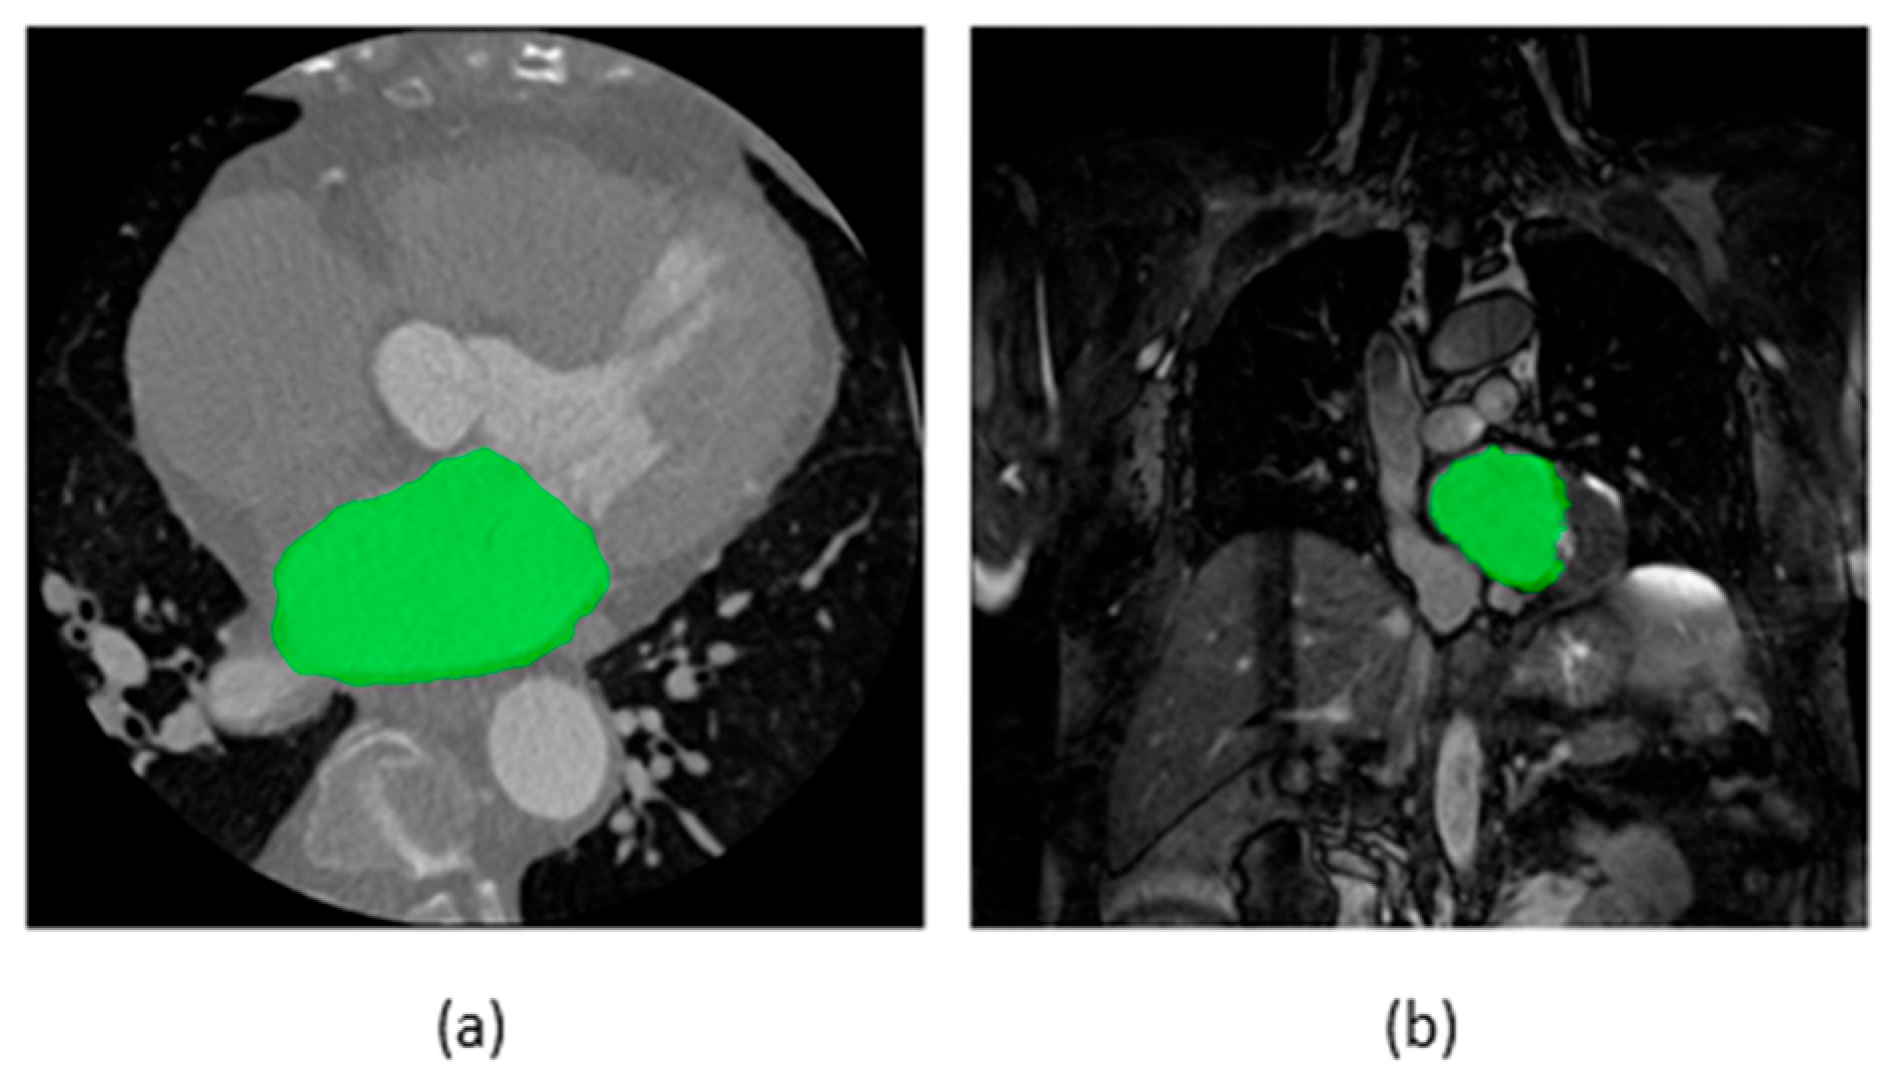

Figure 2 illustrates some examples of segmentation maps of the LA superimposed on raw images of CT and MRI. An AI-based segmentation model performs segmentation by categorizing each pixel of the input images as either belonging to the structure of interest (foreground/positive) or not (background/negative). Table 1 provides a summary of selected publications on AI-based segmentation methods for image-assisted AF care. Notably, the definitions of the structure of interest differ among the datasets used by different publications. For instance, in the 2018 LA segmentation challenge (LASC) dataset [13], currently the largest open-source dataset for LA segmentation on late gadolinium-enhanced MRI (LGE-MRI) in patients with AF, the structure of interest was defined as the pixels within the LA endocardial surface, including the MV and the LAA, as well as the extent of the PV sleeves. In the datasets used in other selected publications, the definitions of the structure of interest vary, including solely the LA [14,15] or various combinations of the LA and its substructures [16,17,18] on contrast-enhanced CT (CECT) or LGE-MRI. In addition, Jin et al. [19] proposed a model for the segmentation of the LAA on CECT, which is desirable for LAA occlusion procedures [20].

Figure 2.

Segmentation maps of the left atrium superimposed on axial slices of (a) computed tomography and (b) magnetic resonance imaging scan. Source of scans: multi-modality whole-heart segmentation [21,22,23].